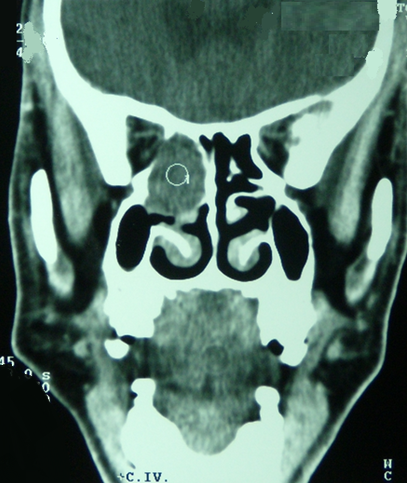

Le lymphome diffus à grandes cellules est un lymphome malin non hodgkinien qui atteint rarement le sinus éthmoïdal. Le pronostic dépend du stade de découverte, de la rapidité du diagnostic et de la prise en charge thérapeutique. Patiente âgée de 64 ans a été admise pour exploration d'une céphalée récente associée à des douleurs oculaires gauches évoluant depuis un mois sans flou visuel ni baisse de l'acuité visuelle. L'examen physique n'a pas révélé de fièvre ni d'adénopathies périphériques. L'endoscopie nasale a trouvé une tumeur du sinus éthmoïdal gaucheinfiltrant la cavité nasale homolatérale. La TDM du massif facial a révélé une formation éthmoïdale gauche de densité tissulaire de 3 cm de grand axe avec amincissement de la paroi interne de l'orbite gauche. L'examen anatomo-pathologique d'une biopsie réalisée à travers la cavité nasale a montré des infiltrats diffus de grands lymphocytes atypiques avec des noyaux hyperchromatiques. L'étude immuno-histochimique a confirmé le diagnostic d'un lymphome Bdiffus à grandes cellules du sinus éthmoïdal. Le bilan d'extension du lymphome était négatif. Le traitement s'est basé sur une radiothérapie couplée à une chimiothérapie. L'évolution était marquée par l'absence d'extension ou de métastases avec un recul de 5 mois.